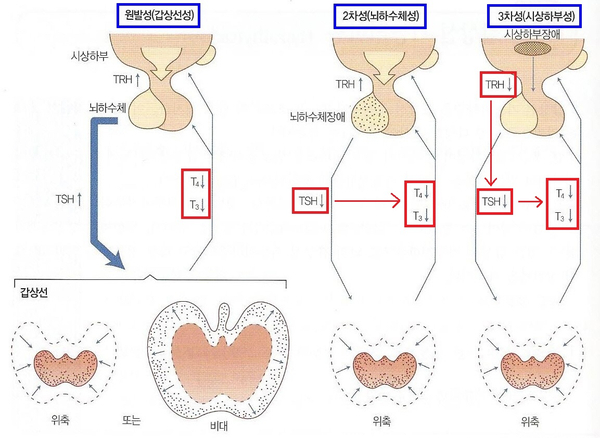

갑상선 호르몬 분비 갑상선 호르몬 분비는 그림과 같이 뇌하수체(TSH), 시상하부(TRH)의 다단계 영향을 받고 있으며 음성 되감기 전에 의해 항진되지 않도록 조절되어 있습니다. 갑상선 기능은 갑상선 호르몬을 생산하는 능력을 말하며, 갑상선 기능 저하증에서는 갑상선 호르몬의 혈중 농도가 낮습니다.갑상선에서 분비되는 갑상선 호르몬의 하루 분비량은 T4(thyroxine)가 80μg으로 가장 많고 T3가 4μg, 비활성형 rT3가 2μg입니다. T4는 간, 신장 등에서 탈요오드화하여 1/3은 T3로, 1/2은 rT3로 전환됩니다.

갑상선기능저하증의 원인별 분류원전성 2차성 3차성 갑상선조직감소호르몬 합성장애 뇌하수체 장애시 상하부 장애 T3, T4감소 TSH감소→ T3, T4감소 TRH감소→ T3, T4감소 갑상선호르몬 분비는 뇌하수체, 시상하부의 다단계 영향을 받고 있으므로 갑상선기능저하증은 장애부위에 따라 원발성(1차성), 2차성, 3차성으로 구분합니다. 각각 갑상선 자체의 장애, 하수체의 장애, 시상하부의 장애가 원인입니다.원자력 발전성은 다시 갑상선 조직의 감소와 갑상선 호르몬 합성 장애로 구분합니다. 전자는 만성 갑상선염(하시모토병 등), 아급성 갑상선염, 갑상선 절제수술, X선 조사 등으로 갑상선 조직이 파괴되거나 절제되어 갑상선 기능이 저하됩니다. 후자는 갑상선의 T3, T4 합성과정 중 특정 단계가 장애를 받아 나타나며 요오드 섭취나 유기화 장애, 축합, thyroglobulin 가수분해 및 합성장애가 원인이 됩니다.갑상선 기능 저하증은 갑상선 호르몬이 부족하기 때문에 보충요법으로 thyroxine(T4제제)을 투여합니다.